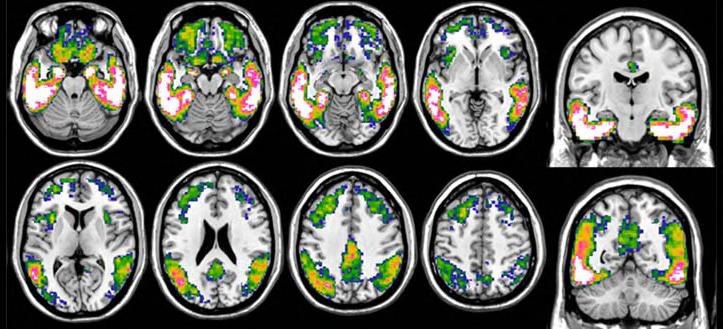

lzheimer’s disease, a common neurodegenerative disorder, results in a gradual deterioration of memory and autonomy. This condition is characterized by the buildup of neurotoxic proteins, specifically amyloid plaques and tau tangles, within the brain. Given the silent progression of these pathological changes over decades, early diagnosis is vital to initiate possible interventions. Now, researchers have demonstrated that tau PET, an innovative imaging method for visualizing the tau protein, can predict cognitive decline in patients with superior accuracy compared to conventional imaging techniques. These are the findings of a study published on August 9, 2023 in Alzheimer’s & Dementia: The Journal of the Alzheimer’s Association, supporting the rapid integration of tau PET into clinical practice for providing early and individualized interventions.

Positron emission tomography (PET), a key diagnostic tool for Alzheimer’s disease, employs injected tracers to visualize specific brain pathologies. While amyloid plaques may not invariably correlate with cognitive or memory impairment, the presence of tau aligns closely with clinical symptoms and significantly influences whether a patient remains stable or deteriorates rapidly. Visualizing tau using imaging techniques has posed challenges due to its intricate structure and lower concentration.

Flortaucipir, a radiotracer approved by the U.S. Food and Drug Administration (FDA) in 2020, binds with the tau protein. This tracer facilitates the detection of tau accumulation and its spatial distribution in the brain, enabling precise evaluation of its role in the clinical manifestation of the disease.

Scientists from the University of Geneva (UNIGE, Geneva, Switzerland; www.unige.ch) and the Geneva University Hospitals (HUG, Geneva, Switzerland; www.hug.ch) embarked on a study to determine which imaging technique—amyloid PET, glucose metabolism PET, or tau PET—best predicted future cognitive decline in Alzheimer’s disease. The study revealed that while all PET measures correlated with the presence of cognitive symptoms, validating their role as strong indicators of Alzheimer’s disease, tau PET exhibited the greatest predictive capacity for cognitive decline rates, even in individuals with minimal symptoms. These findings support incorporating tau PET into routine clinical assessments to assess individual prognosis and select the most appropriate therapeutic plan for each patient.

“This breakthrough is crucial for better management of Alzheimer’s disease. Recently, drugs targeting amyloid have shown positive results. New drugs targeting the tau protein

also look promising,” said Associate Professor Valentina Garibotto who directed the research. “By detecting the pathology as early as possible, before the brain is further damaged, and thanks to new treatments, we hope to be able to make a greater impact on patients’ future and quality of life.”

Image: Tau imaging with 18F-Flortaucipir PET in Alzheimer’s disease (Photo courtesy of UNIGE)